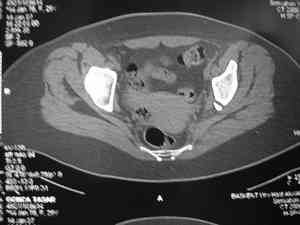

прилагаю пример с такой же давностью травмы, репонировали аппаратом